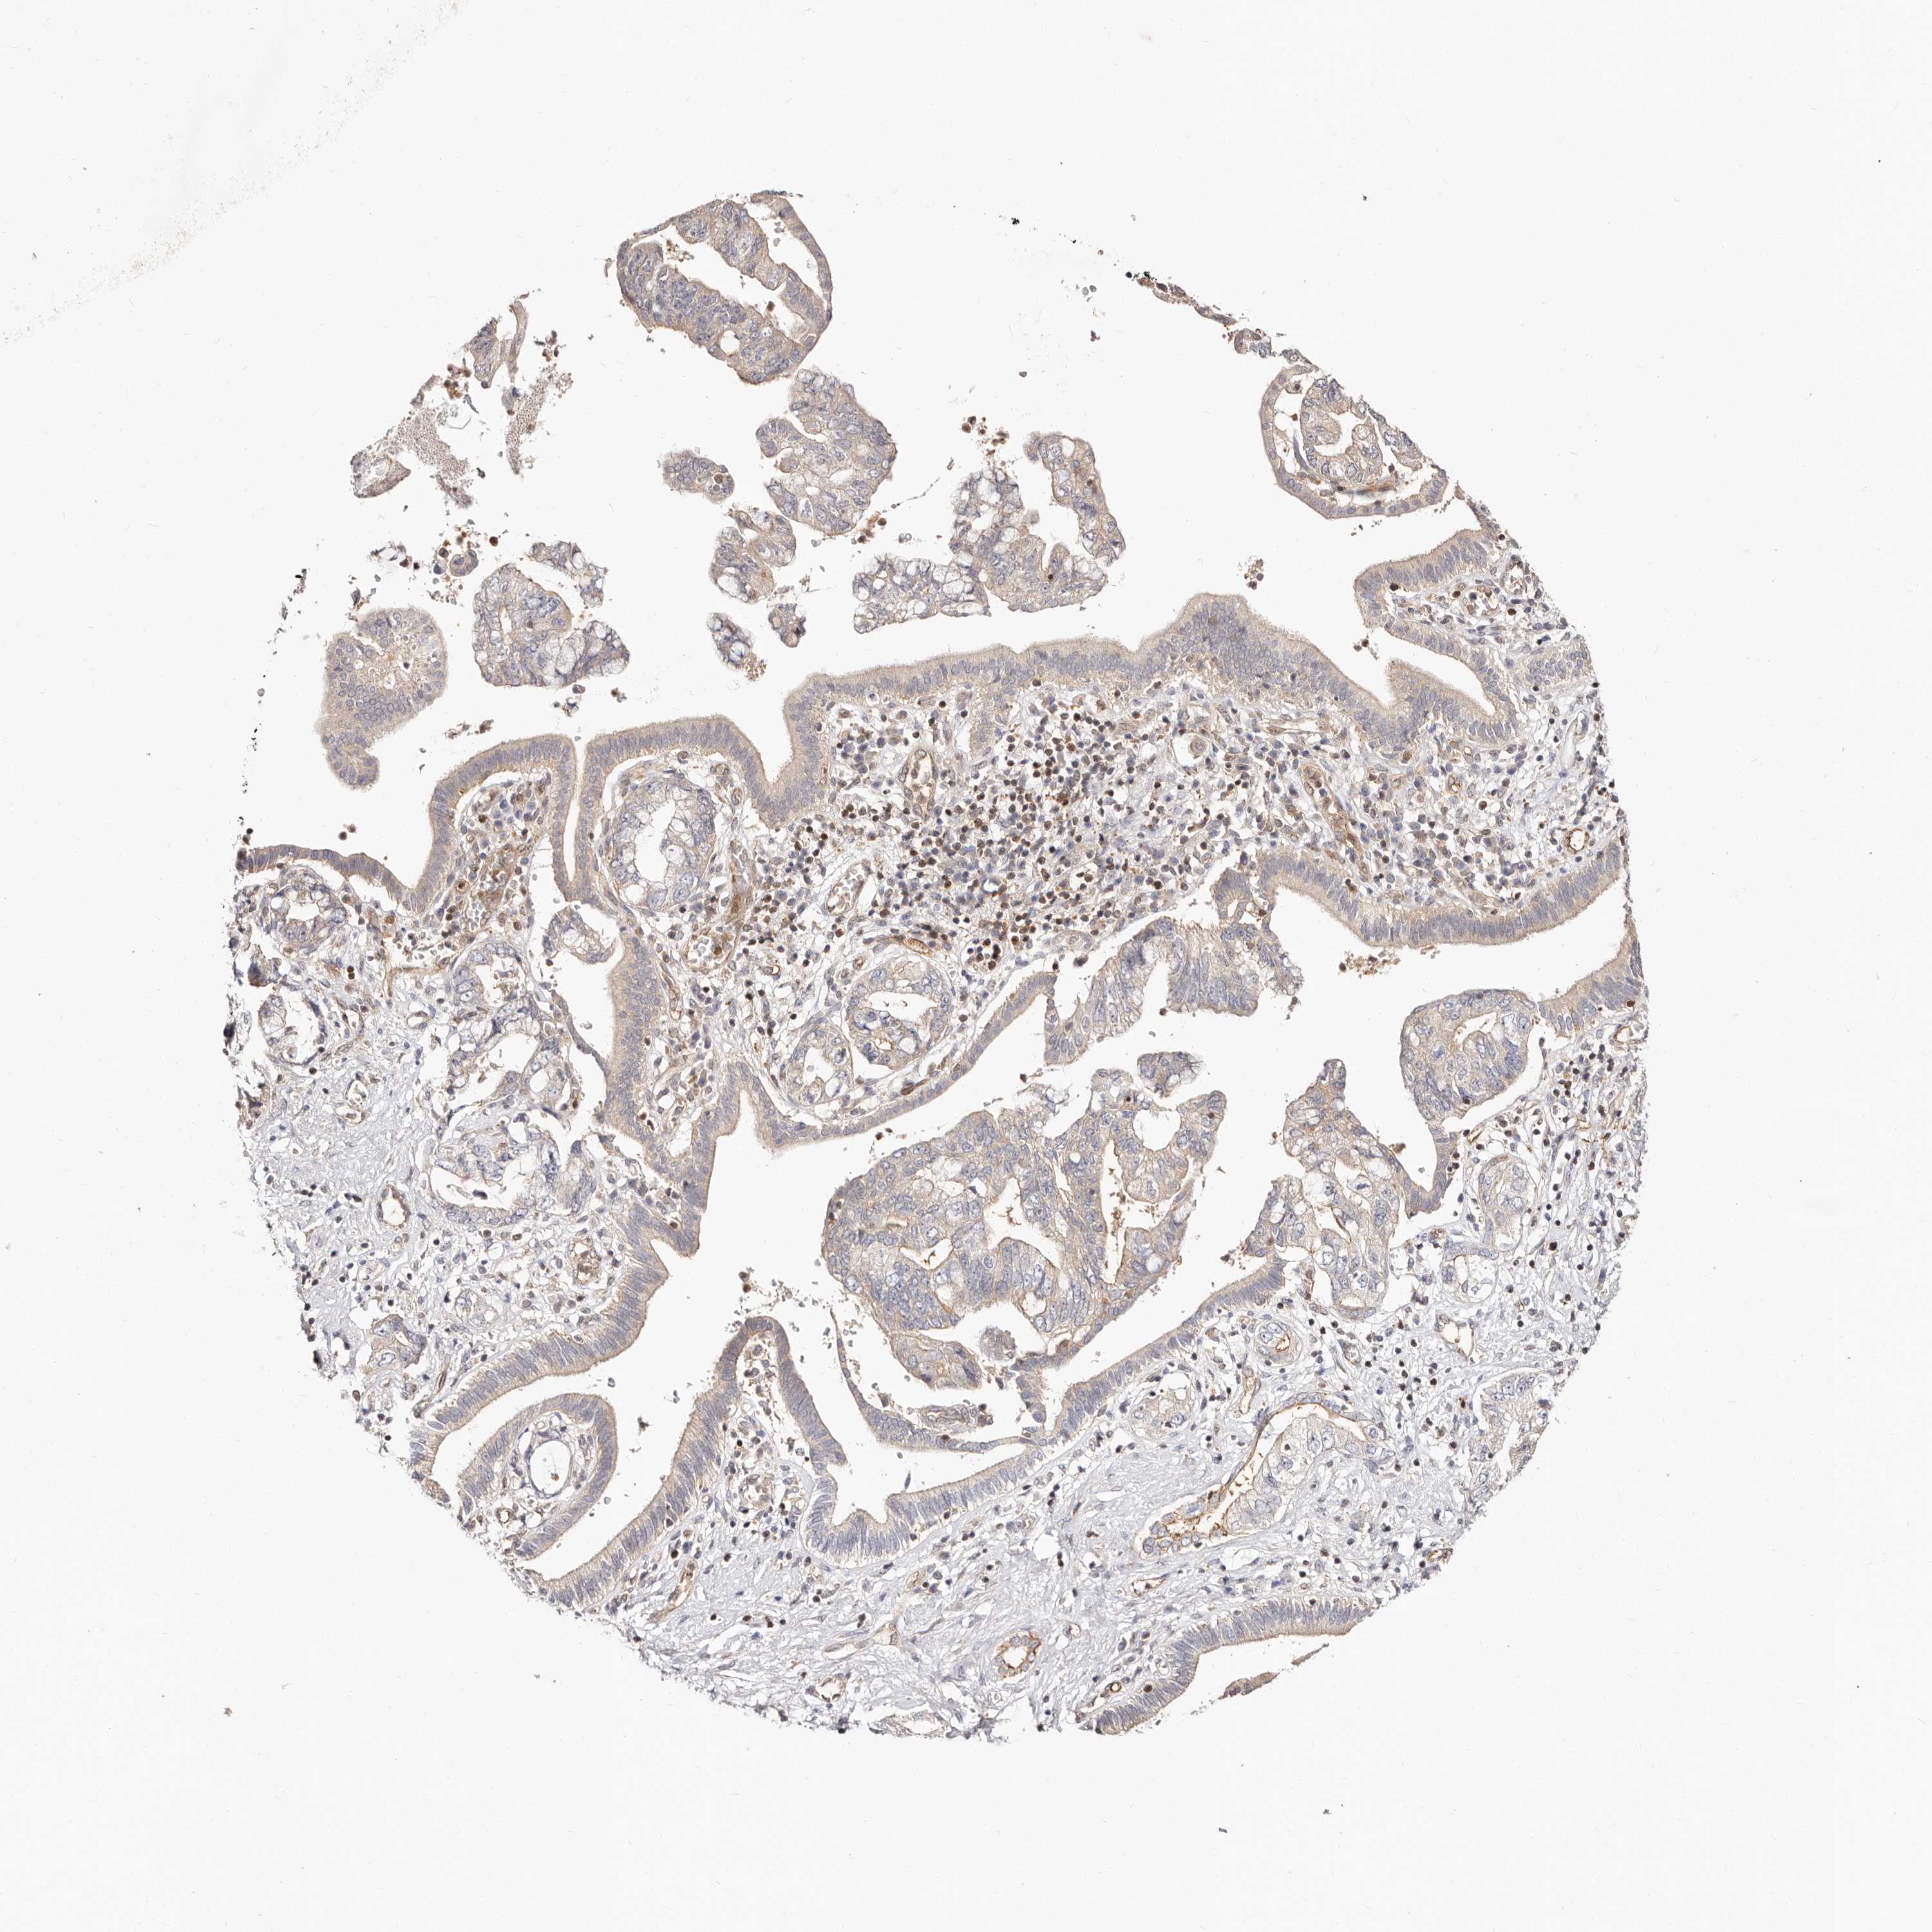

PANCREATIC CANCER - Protein expressioni

A mouse-over function shows sample information and annotation data. Click on an image to view it in a full screen mode. Samples can be filtered based on level of antibody staining by selecting one or several of the following categories: high, medium, low and not detected. The assay and annotation is described here.

Note that samples used for immunohistochemistry by the Human Protein Atlas do not correspond to samples in the TCGA dataset.

Antibody stainingi

Antibody staining in the annotated cell types in the current human tissue is reported as not detected, low, medium, or high, based on conventional immunohistochemistry profiling in selected tissues. This score is based on the combination of the staining intensity and fraction of stained cells.

Each image is clickable and will lead to virtual microscopy that enables deeper exploration of all samples and also displays staining intensity scores, fraction scores and subcellular localization as well as patient and tissue information for each sample.

Staining

High

Medium

Low

Not detected

Intensity

Strong

Moderate

Weak

Negative

Quantity

>75%

75%-25%

<25%

None

Location

Nuclear

Cytoplasmic/membranous

Cytoplasmic/membranous,nuclear

Adenocarcinoma, NOS